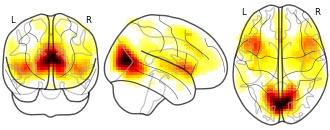

"description": "Abnormal gray matter in BPD. Brain regions with significant heterogeneity (i.e. between-study variance) in the comparison of patients with BPD and healthy controls. Results are thresholded at at p<.005 & k>20. Note: Results are based on meta-analysis of group comparisons. Note2: Results were updated (see Erratum for this publication)",